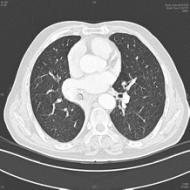

牟向东主任告诉我们,当时门诊初步诊断这位患者是支气管内阻塞导致的肺不张。「我们因此给患者进行了全麻下支气管镜检查,发现他的右肺中间段支气管被肿物完全阻塞,并且有较多黏痰,反复吸痰治疗后,应用激光烧灼肿物,然后应用冷冻探头将中午取出;其后又发现右肺中叶支气管已完全被结石堵塞,随即应用高能激光反复治疗,然后综合应用冷冻、电烧、电圈套器等方法,终于将这块肿物分次取出,并留取了组织送检病理。后来的病理报告显示,该患者的右肺中叶支气管肿物是『肺错构瘤』。肺错构瘤长在支气管里这种情况极为少见,属于罕见病,绝大多数都是长在肺内。」

图为长在患者支气管里的肺错构瘤

图片由牟向东主任提供